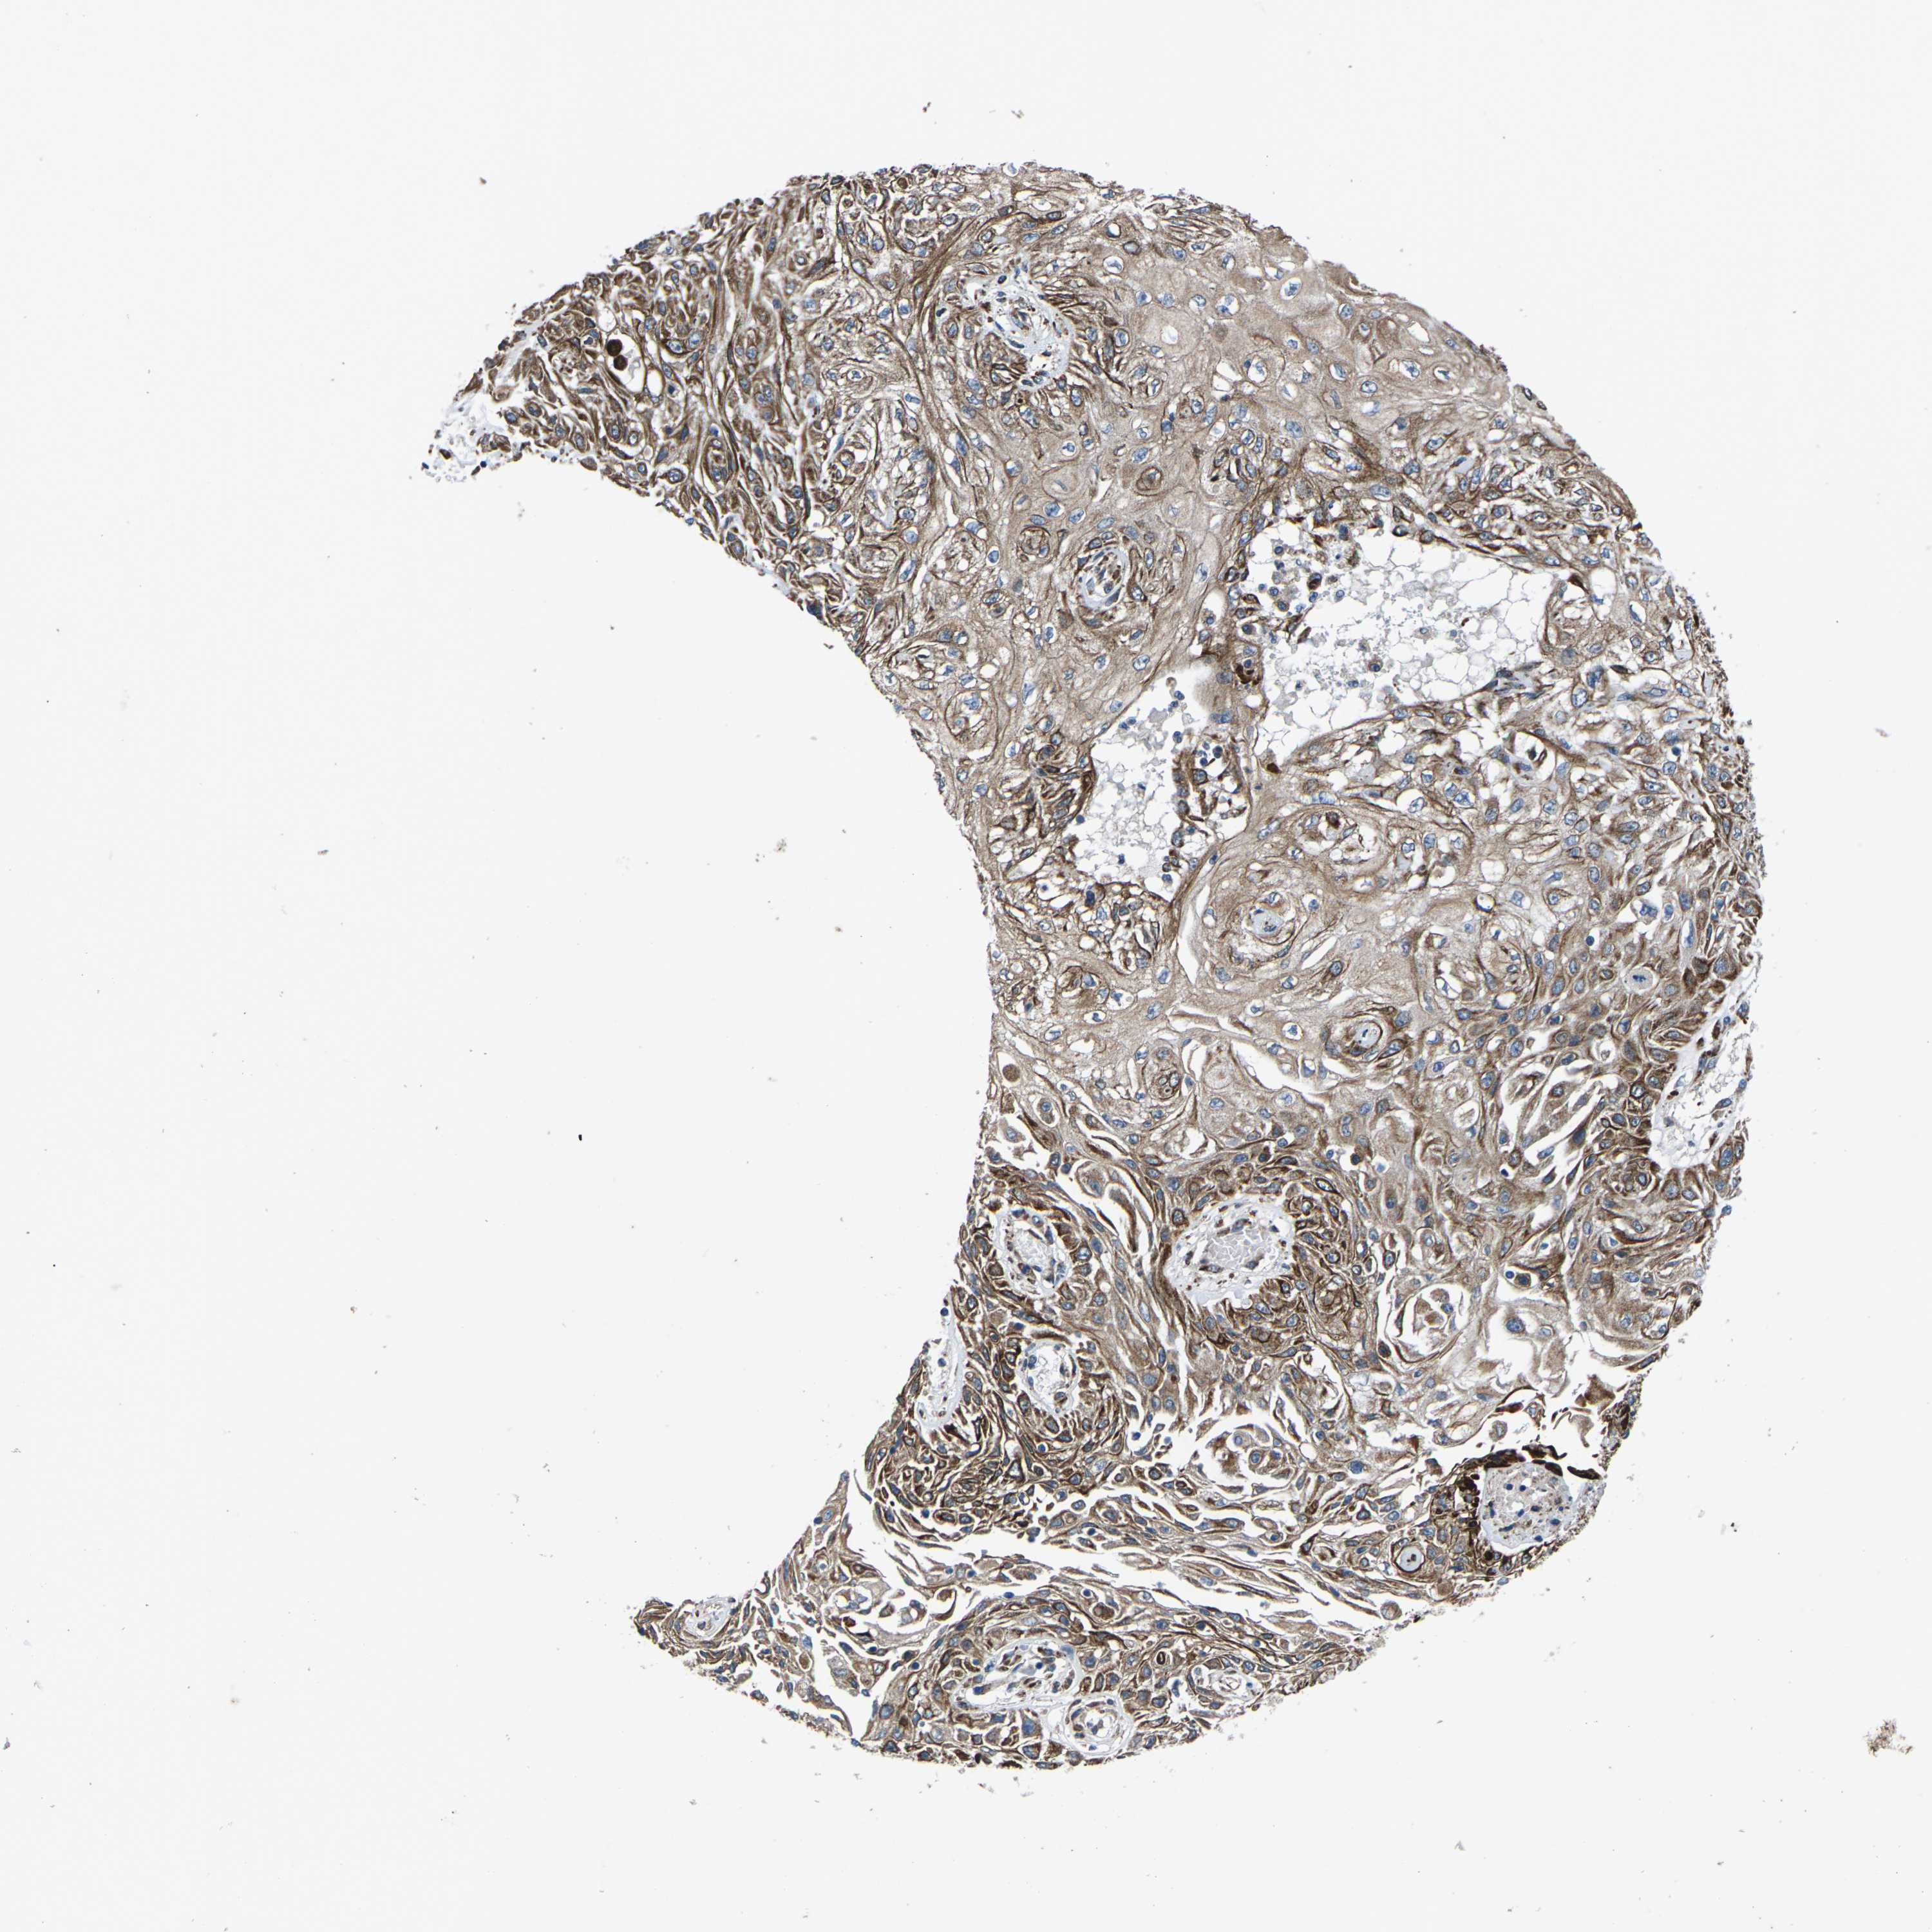

CANCER SKIN CANCER Show tissue menu

Basal cell and squamous cell cancer

SKIN CANCER - Protein expressioni

A mouse-over function shows sample information and annotation data. Click on an image to view it in a full screen mode. Samples can be filtered based on level of antibody staining by selecting one or several of the following categories: high, medium, low and not detected. The assay and annotation is described here.

Each image is clickable and will lead to virtual microscopy that enables deeper exploration of all samples and also displays staining intensity scores, fraction scores and subcellular localization as well as patient and tissue information for each sample.

Antibody CAB014883

Staining

High

Medium

Low

Not detected

Intensity

Strong

Moderate

Weak

Negative

Quantity

>75%

75%-25%

<25%

None

Location

Nuclear

Cytoplasmic/membranous

Cytoplasmic/membranous,nuclear

Squamous cell carcinoma in situ, NOS

Squamous cell carcinoma, NOS

Basal cell carcinoma

Adnexal tumor, benign